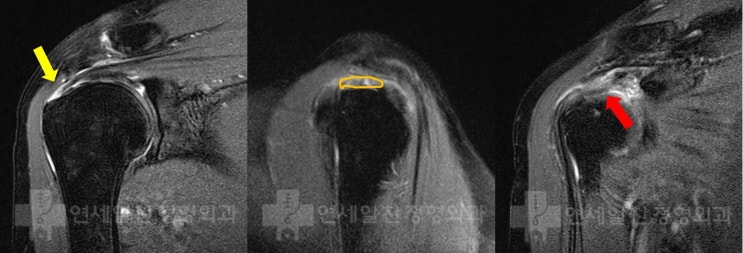

반카르트 봉합술 후 결과 - MRI 상 해부학적 복원

이전에 반카르트 봉합술을 해부학적으로 복원한 환자의 결과에 대해 알아보자 환자는 수술 후 6주차에 수술...